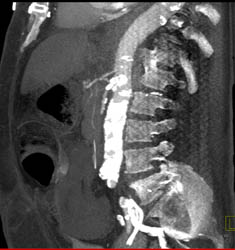

Gastric and Esophageal Emphysematous Changes With Portal Vein Air Compatible With Massive Infarction